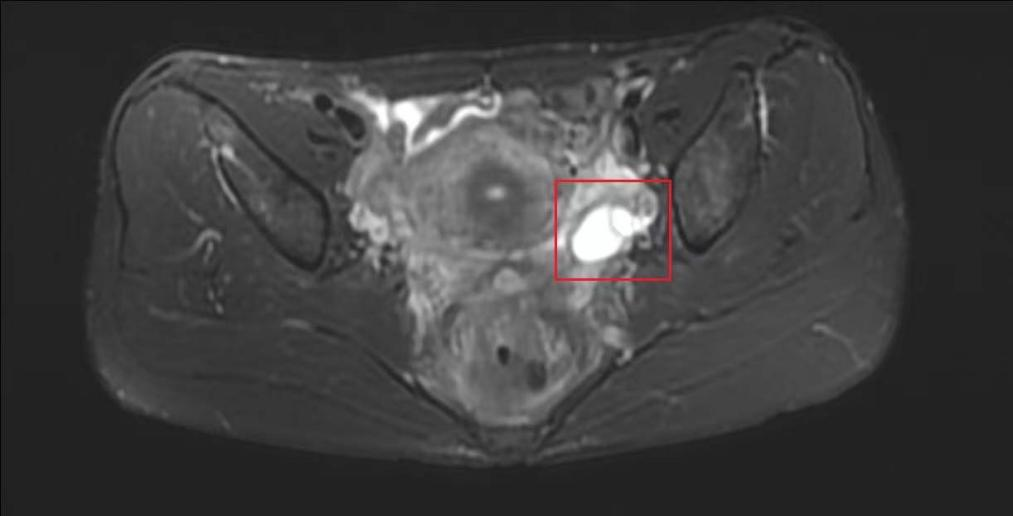

“每天大便7、8次,每次都非常痛。”王女士摇摇头说道,“每次量很少,小便也有困难,而且肛门坠胀感十分强烈。”王女士多次在其他医院胃肠外科治疗效果不佳,到南方医科大学中西医结合医院就医后接受结肠镜、超声肠镜等检查均未见异常,但在下腹部MR扫描时,发现“子宫直肠窝数个囊状异常信号,考虑巧克力囊肿”以及“左附件区囊性病变,考虑卵巢巧克力囊肿”。曾朝阳介绍,巧克力囊肿指的是陈旧性积血的囊肿,因为呈褐色,黏稠如糊状,似巧克力,故被称为“巧克力囊肿”。

左附件区囊性病变

妇科曾朝阳主任在会诊王女士时,仔细追问病史,得知她有痛经病史3年且症状逐渐加重。进行妇检发现王女士子宫后方、直肠前方可触及大小约6cmx4cmx3cm的实性不规则包块,且向两侧骨盆壁靠近,活动差,触痛;肛查发现距肛门约10cm处可触及不规则肿物,直肠粘膜面光滑,无指套带血;阴道彩超结果:子宫直肠窝混合回声包(50mmx21mm)。结合多项检查结果,曾朝阳考虑王女士为“深部浸润型子宫内膜异位症”,也就是俗话说的发生在盆腔上的巧克力囊肿。通过望闻问切,结合症状及舌脉象,中医辨证为“气滞血瘀证”。